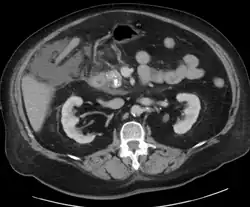

Acute exudative pancreatitis on CT scan

A contrast-enhanced CT scan is usually performed more than 48 hours after the onset of pain to evaluate for pancreatic necrosis and extrapancreatic fluid as well as predict the severity of the disease. CT scanning earlier can be falsely reassuring.